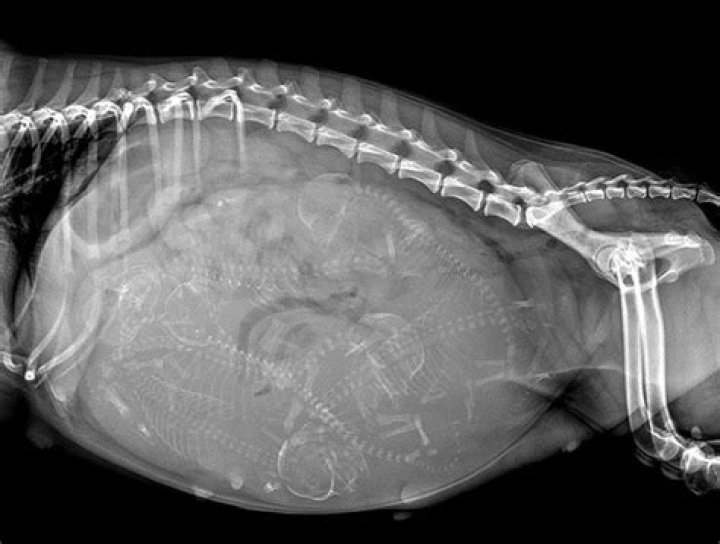

Does USPS scan all packages for drugs?

Postal inspectors can screen packages to check for drugs like marijuana and other substances. Some people may attempt to send drugs through the mail because they believe the Fourth Amendment protects them from having their packages searched.

Once the package is 'seized', it may be examined by a drug dog, and a warrant will be issued to open the package should the dog alert for the presence of drugs (typically, the post office will line up 6 packages, five which they know do not contain drugs, and the suspected package).